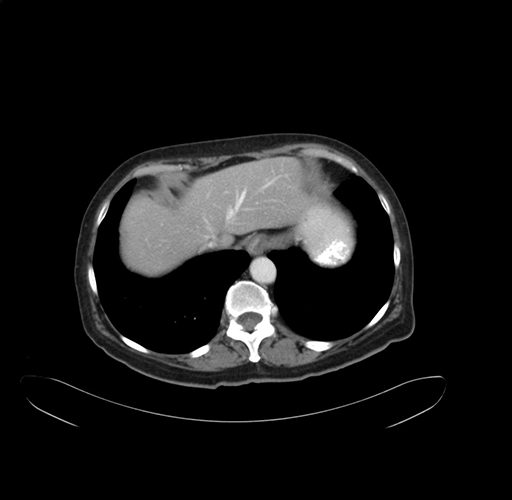

Pre-Chemo: Axial Venous